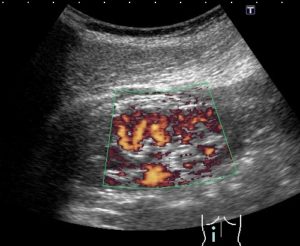

Помимо стандартного ультразвука, существуют и другие специальные процедуры. При диабете нередко используют допплерографию. Она помогает хорошо визуализировать полые органы – кровеносные сосуды.

- Допплерография: позволяет динамически визуализировать потоки жидкости (особенно кровоток). Основана на принципе, что ультразвуковые волны с определенной частотой излучаются в ткань и рассеиваются там на циркулирующих эритроцитах. Допплеровская сонография используется для оценки скорости кровотока и, таким образом, позволяет диагностировать патологические сосудистые изменения (например, артериосклероз и вазоконстрикцию), дефекты сердца и клапана;

- Цветная допплерография: это одна из самых важных диагностических процедур в ангиологии, потому что она позволяет с высокой точностью выявить различные патологии сосудов. Цветная УЗИ производит цветные изображения. Она помогает выявить аневризмы и кисты различного размера. Характер цвета также позволяет оценить скорость кровотока и, следовательно, тяжесть вазоконстрикции. Также могут быть визуализированы сосудистые окклюзии.

В области сонной артерии или паха сосуды могут отображаться настолько надежно, что часто можно отказаться от дальнейших процедур визуализации. При диагностике варикозного расширения вен сонография почти полностью вытеснила флебографию.